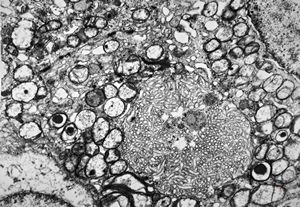

F,50y. | progressive multifocal leukoencephalopathy- viral particles in a glial cell

F,50y. | progressive multifocal leukoencephalopathy- viral particles in a glial cell

F,50y. | progressive multifocal leukoencephalopathy- viral particles in a glial cell